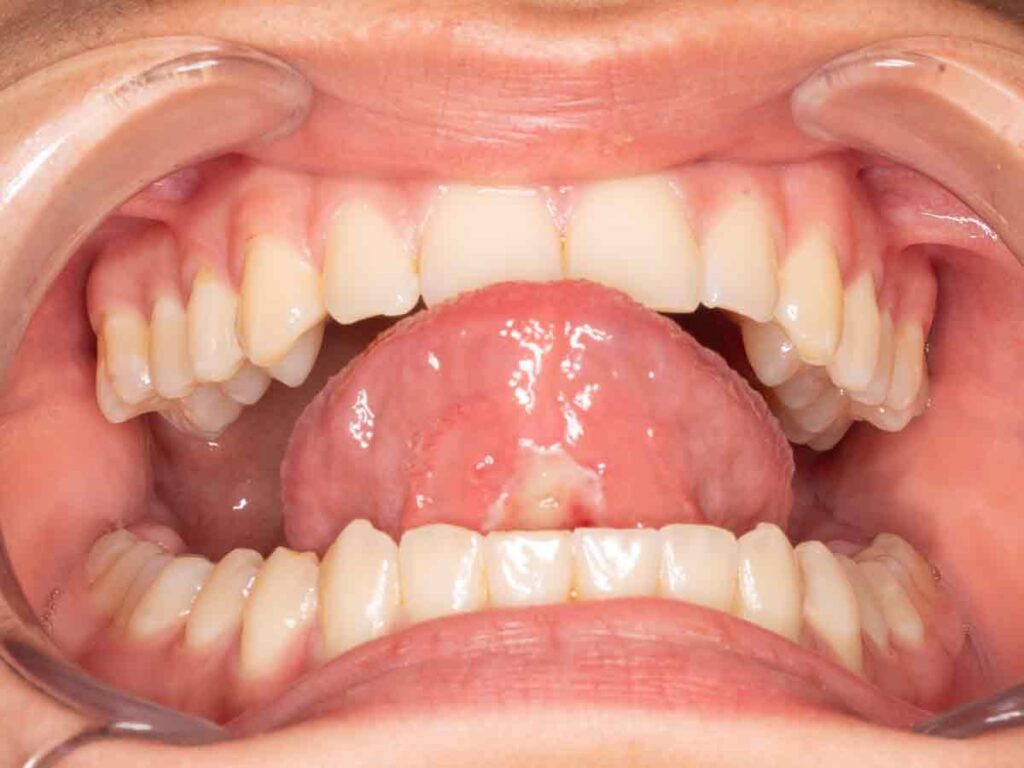

Resección frenillo postoperatorio 18 horas

Resección frenillo postoperatorio 18 horas sin dolor ni sutura

En el control postoperatorio precoz se observó ausencia de dolor y de hemorragia. La presencia de fibrina en la zona intervenida correspondía a una evolución normal y esperable.